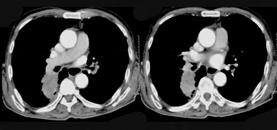

- 单项选择题72岁,男, 呼吸急促、气喘4个月,请结合胸片和CT, 选出最可能的诊断 ( )

A、肺癌

B、错构瘤

C、肺结核

D、韦格肉芽肿

E、支气管腺瘤